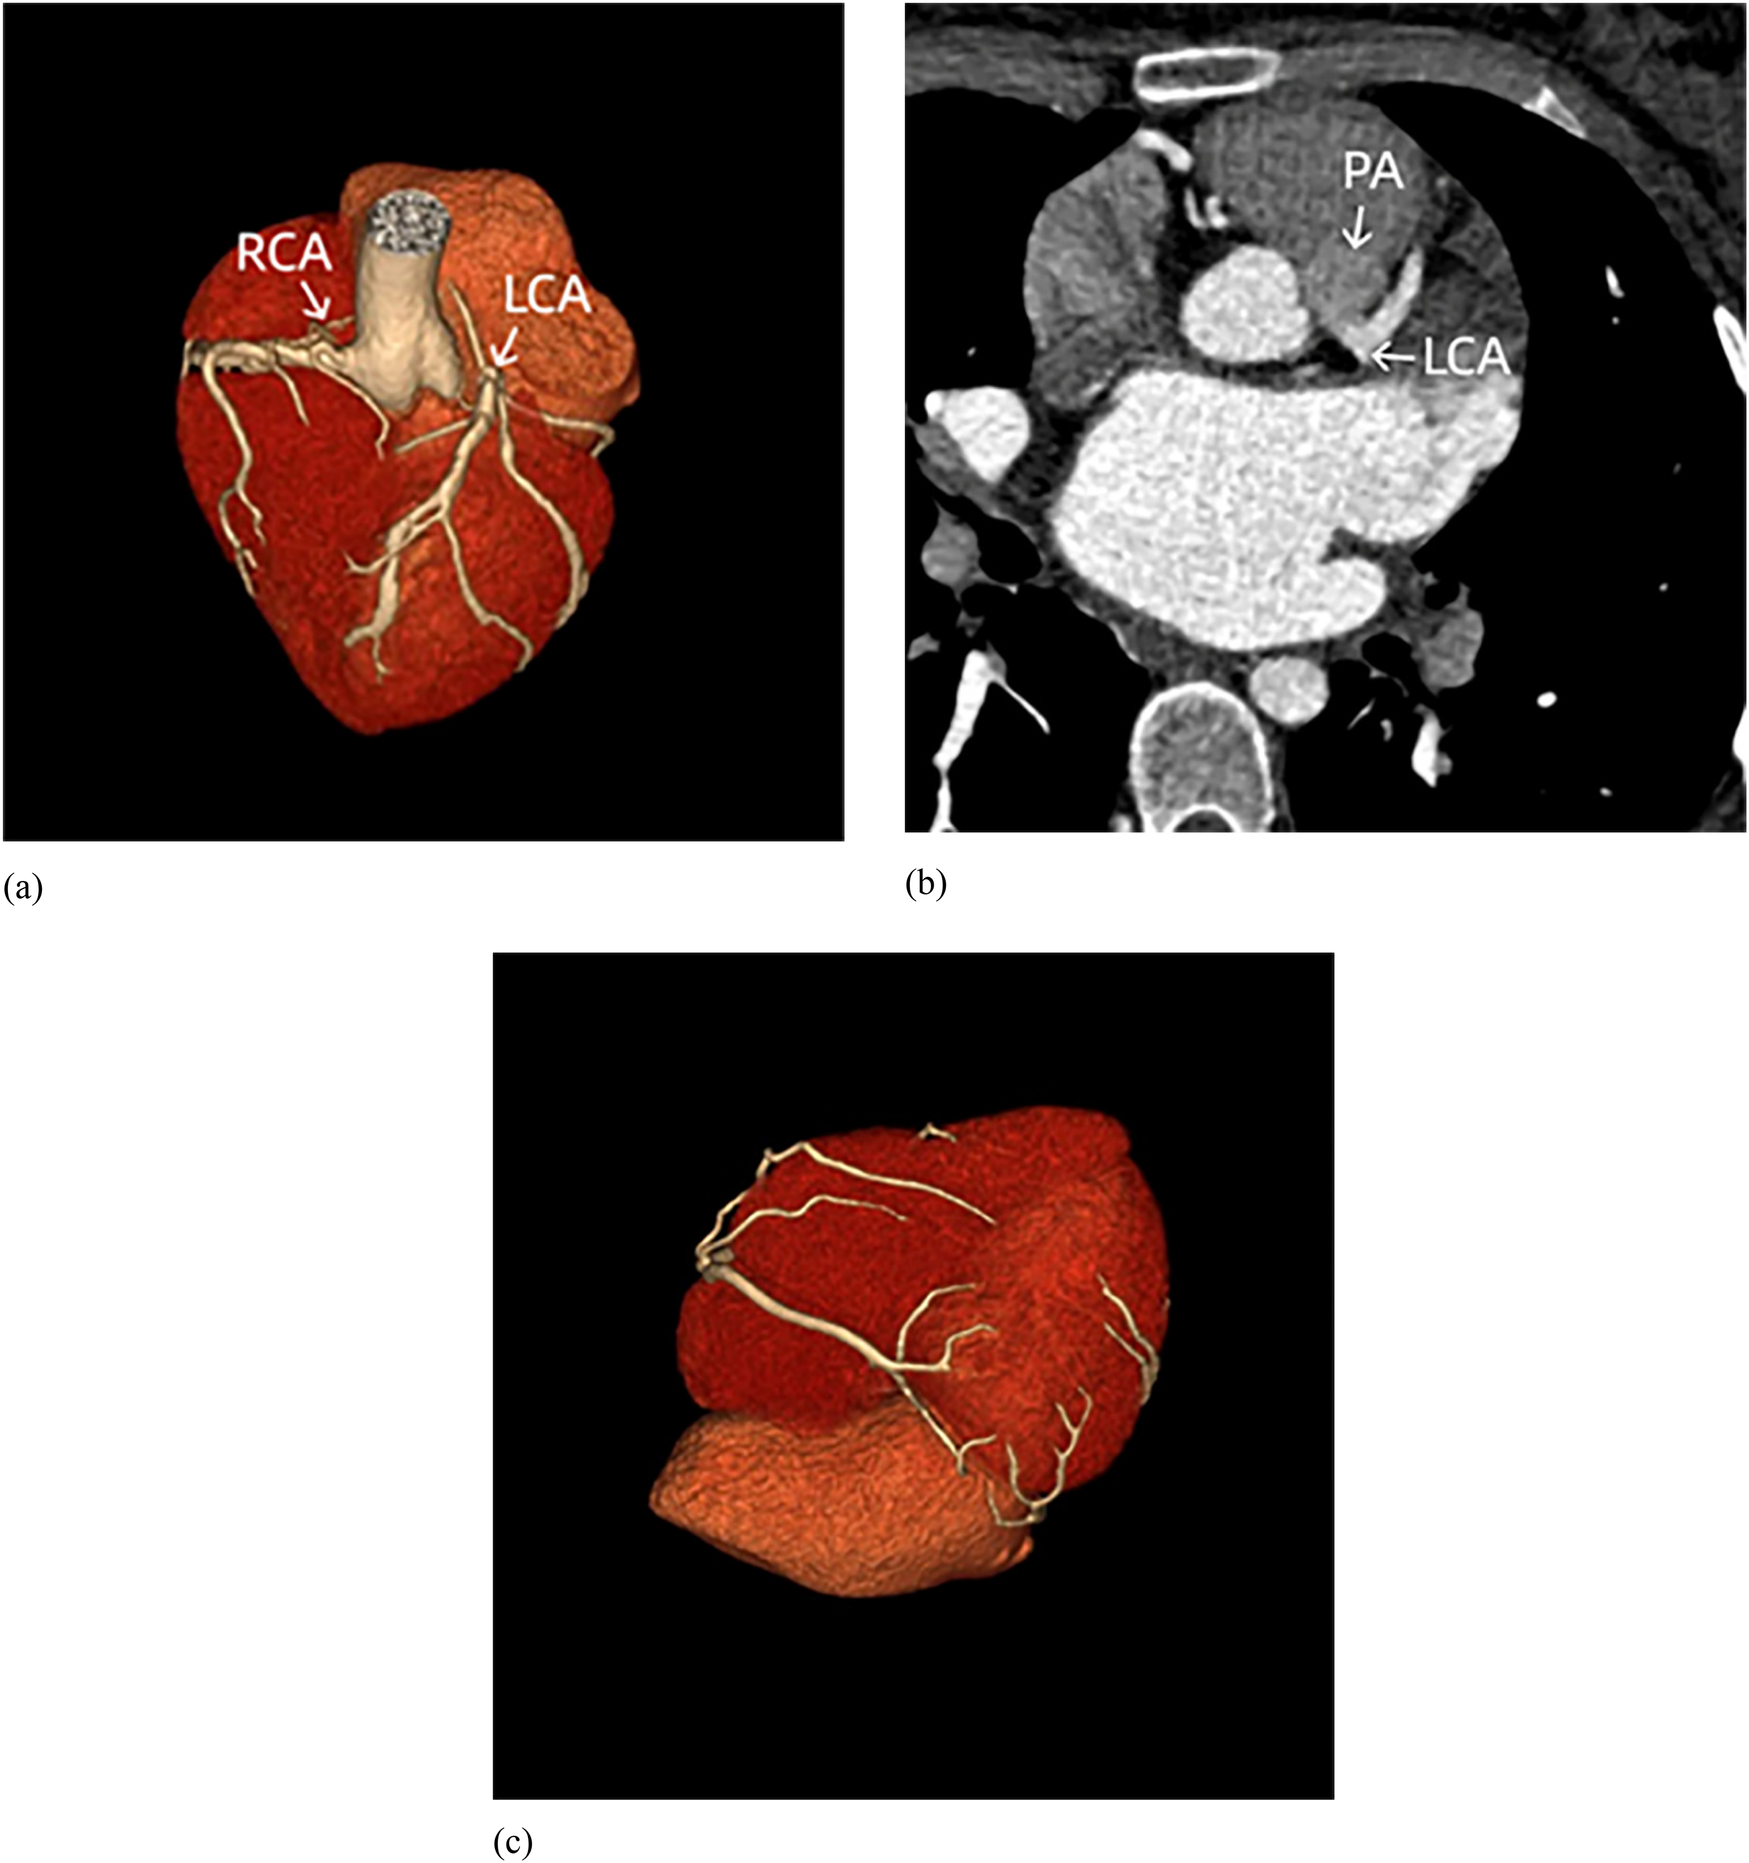

A 28-year-old female was admitted to our hospital due to atrial fibrillation and pulmonary hypertension. She first experienced palpitations at the age of 20, and an ECG confirmed atrial fibrillation. Despite treatment with amiodarone, her condition escalated from paroxysmal to persistent atrial fibrillation. She has not undergone anticoagulation therapy. At the age of 27, her exercise tolerance notably declined, accompanied by chest pain post-activity, and suffered an ischemic stroke. The echocardiography estimated the pulmonary artery systolic pressure (PASP) at 67 mmHg. Although she was treated with oral ambrisentan, her exercise tolerance did not improve, leading her to seek further treatment at our institution. Her medical history was clear of hypertension, diabetes, hyperlipidemia, smoking, drug or food allergies, stimulant use, or any family history of cardiovascular disease. On physical examination, her vital signs were normal, with P2 > A2, irregular heart rhythm, and mild edema in both lower limbs. The patient's thyroid function, hepatic and renal function, high-sensitive troponin I were normal. The N-terminal pro-B-type natriuretic peptide (NT-proBNP) level was elevated at 2,180 pg/ml (normal range: 0–125 pg/ml). Her ECG showed atrial fibrillation with ST-segment depression in leads I, aVL and V4–V6, and poor R-wave progression in leads V1–V3 (Figure 1). Right heart catheterization (RHC) revealed the pulmonary artery systolic pressure, diastolic pressure, and mean pressure were 42 mmHg, 22 mmHg, and 30 mmHg, respectively. The pulmonary capillary wedge pressure (PCWP) was 23 mmHg, and the pulmonary vascular resistance (PVR) was measured at 1.26 Wood Units, suggesting the pulmonary hypertension was related to left heart disease (4). Her transthoracic echocardiography showed a left ventricular ejection fraction of 65%, with an enlarged left atrium with dimensions measuring 48 mm antero-posteriorly, 61 mm superior-inferiorly, and 50 mm transversely, and suspected origin of the LCA from the pulmonary artery. Additionally, the right coronary artery is dilated, and there is visible extensive blood flow communication between the left and right coronary arteries within the myocardium. Echocardiographic evaluation also revealed mild left ventricular enlargement, with left ventricular end-diastolic dimension 51.2 mm and left ventricular end-diastolic volume indexed 74.31 ml/m². Although no regional wall motion abnormalities were observed, the impaired diastolic function (E/e′ ratio 12) indicates chronic ischemia of the left ventricle. There are also signs of right heart dysfunction to chronic pulmonary hypertension with reduced tricuspid annular plane systolic excursion (TAPSE) 12 mm (Figure 2). Further coronary computed tomography angiography (CTA) and coronary angiography showed the left main coronary artery (LMCA) originating from the pulmonary artery, with multiple connections between the distal left and right coronary arteries, and a right coronary to left ventricle fistula (Figure 3 and Supplementary Video S1). Based on these observations, we thought that her clinical manifestations were due to anomalous coronary origin, specifically the abnormal origin of the left coronary artery from the pulmonary artery. The left atrium, mainly supplied by the left circumflex branch (LCX), suffered from prolonged ischemia, leading to structural and electrophysiological remodeling and subsequently to atrial fibrillation and heart failure with preserved ejection fraction (HFpEF), resulting in left heart failure-related pulmonary hypertension, and stroke. She underwent surgery intervention under general anesthesia with hypothermic cardiopulmonary bypass, including the LMCA repositioning and radiofrequency ablation for atrial fibrillation. Postoperative medications included warfarin and aspirin for thromboembolic prophylaxis, amiodarone for rhythm stabilization, and dapagliflozin for optimization in HFpEF phenotype. She was followed up six months after surgery. She regained sinus rhythm, demonstrated a significant improvement in exercise tolerance, and showed a decrease in NT-proBNP levels to 233 pg/ml. Echocardiography revealed a reduction in left atrial size to dimensions of 48 mm × 61 mm × 50 mm (antero-posterior × superior-inferior × transverse diameters) and a decreased estimated PASP from 60–47 mmHg. The timeline of the diagnosis and treatment of the patient is shown in Figure 4.

Figure 3. Coronary CT. (a) The right coronary artery (RCA) originates from the aortic root, while the left coronary artery (LCA) originates from the pulmonary artery (without pulmonary artery reconstruction). (b) The LCA originates from the pulmonary artery (PA). (c) Extensive communications exist between LCA and RCA.